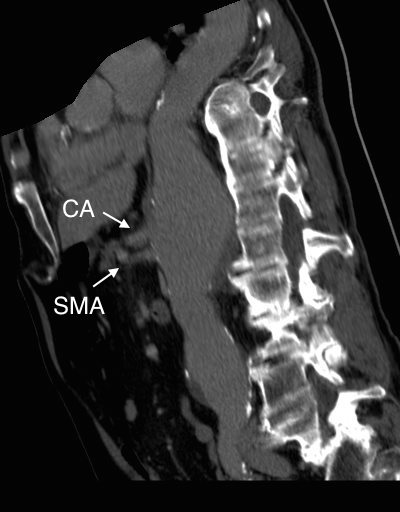

The patient had a 8cm sphere shaped aneurysm arising in the transdiagphragmatic aorta, leaking into the right pleural cavity.

The patient was otherwise a healthy middle aged man with risk factors of smoking and hypertension. The centerline reconstructions showed the thoracic aorta above the aneurysm to be around 20mm in diameter and same below, with the celiac axis and superior mesenteric artery in the potential seal zone of a stent graft. The only plaque seen was around the level of the renal arteries and was focal and calcified. Looking at the list I had made as a comment to the Linked-In post, I realized that I really only had one viable option.

Open repair, usually the most expeditious option, was made challenging by the right hemothorax, making a left thoracotomy hazardous if the lung had to be deflated. Cardiopulmonary bypass would have to be arranged for, and that adds a metabolic hit that greatly raises the stakes. Of the endovascular solutions, the only viable option was TEVAR to exclude the rupture and debranching of the celiac axis and superior mesenteric artery. To those who would advocate for parallel grafts, there was no room in the normal 20mm diameter aorta. And branch systems for rupture are some time in the future. Also, the patient was becoming hypotensive. So the planned operation was first TEVAR to stop the bleeding, and then open surgical debranching. A hybrid repair.